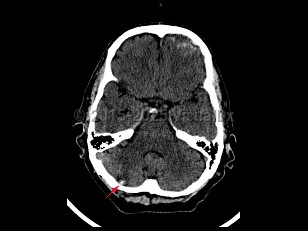

A traumatic injury to the cerebellum occurring when there is forceful contact with the occipital area and surrounding cranium, particularly bony ridges, leading to cerebellar edema and/or punctate hemorrhages. Characterized by dizziness, drowsiness, dysarthria, ataxia, loss of consciousness, and coma. Other signs and symptoms include fatigue, malaise, nystagmus, vertigo, and mydriasis. Associated with basilar skull fracture, cerebellar hemorrhage, traumatic hematoma, subarachnoid hemorrhage, and traumatic brain injury.

Management includes careful assessment and monitoring of symptoms and level of consciousness, mindful that there can be delayed deterioration after cerebellar contusion, which increases risk for complications and death following brain trauma. Wide craniectomy and internal decompression may be advised.

Cerebellar contusion

Cerebellar contusion